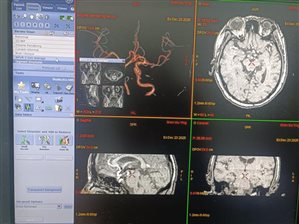

躺在磁共振机器里,患者可能会觉得时间漫长又陌生。而在操作间里,工作人员的眼睛紧紧盯着屏幕,密切关注着检查的每一个环节。他们根据不同的检查部位和目的,精心调整扫描参数,力求获取最清晰、最准确的图像。每一次扫描结束,他们都会仔细查看初步图像,判断是否需要进行补充扫描或调整扫描方案。

检查结束后,患者带着忐忑的心情离开,而工作人员的工作还远未结束。他们要将获取的大量图像数据传输到后处理工作站,进行细致的图像重建和处理。这就像是一场精密的艺术创作,通过各种软件工具,将原始图像转化为医生能够清晰解读的影像资料,再从阅片机上把一幅幅图片认真比对查看,锁定异常信号后,加以分析判断给出合适的诊断。